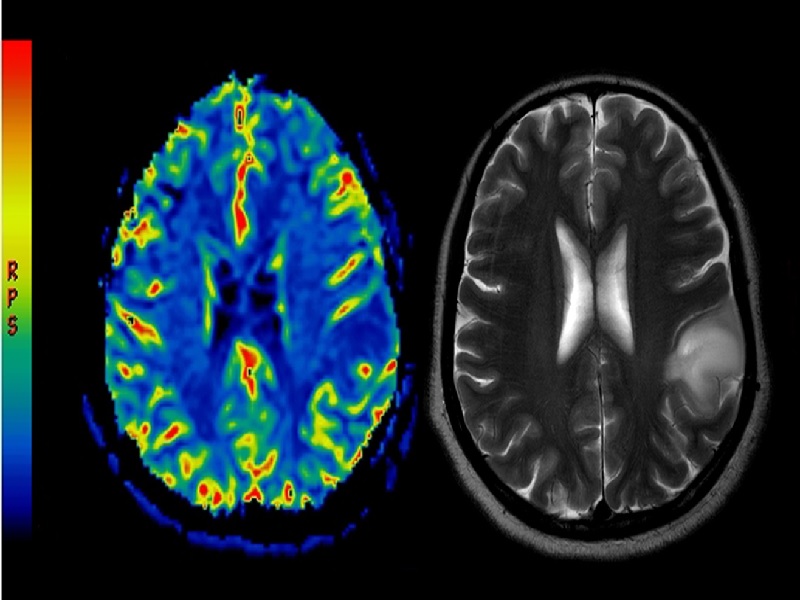

Une Tumeur Au Cerveau Peut Elle Disparaitre Cette IA peut détecter une tumeur au cerveau en deux minutes